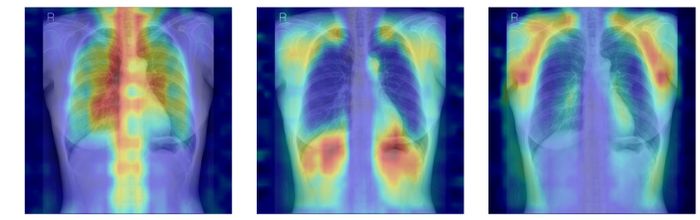

흉부X선에서 파운데이션 모델이 골다공증 판독을 위해 주목한 영역을 시각화한 이미지 ⓒ서울대병원

뼈를 모두 가린 상태에서 특정 뼈 부위를 추가해 성능이 얼마나 향상하는지 확인하는 ‘차단 분석 방식(Δbone)’과 Grad-CAM으로 나타난 AI의 주목 영역이 실제 뼈 위치와 얼마나 일치하는지를 계산하는 ‘유의성 지도 방식(IoUbone)’을 통해, AI가 임상적으로 중요한 뼈 구조를 근거로 판단하는지를 정량적으로 검증했다.